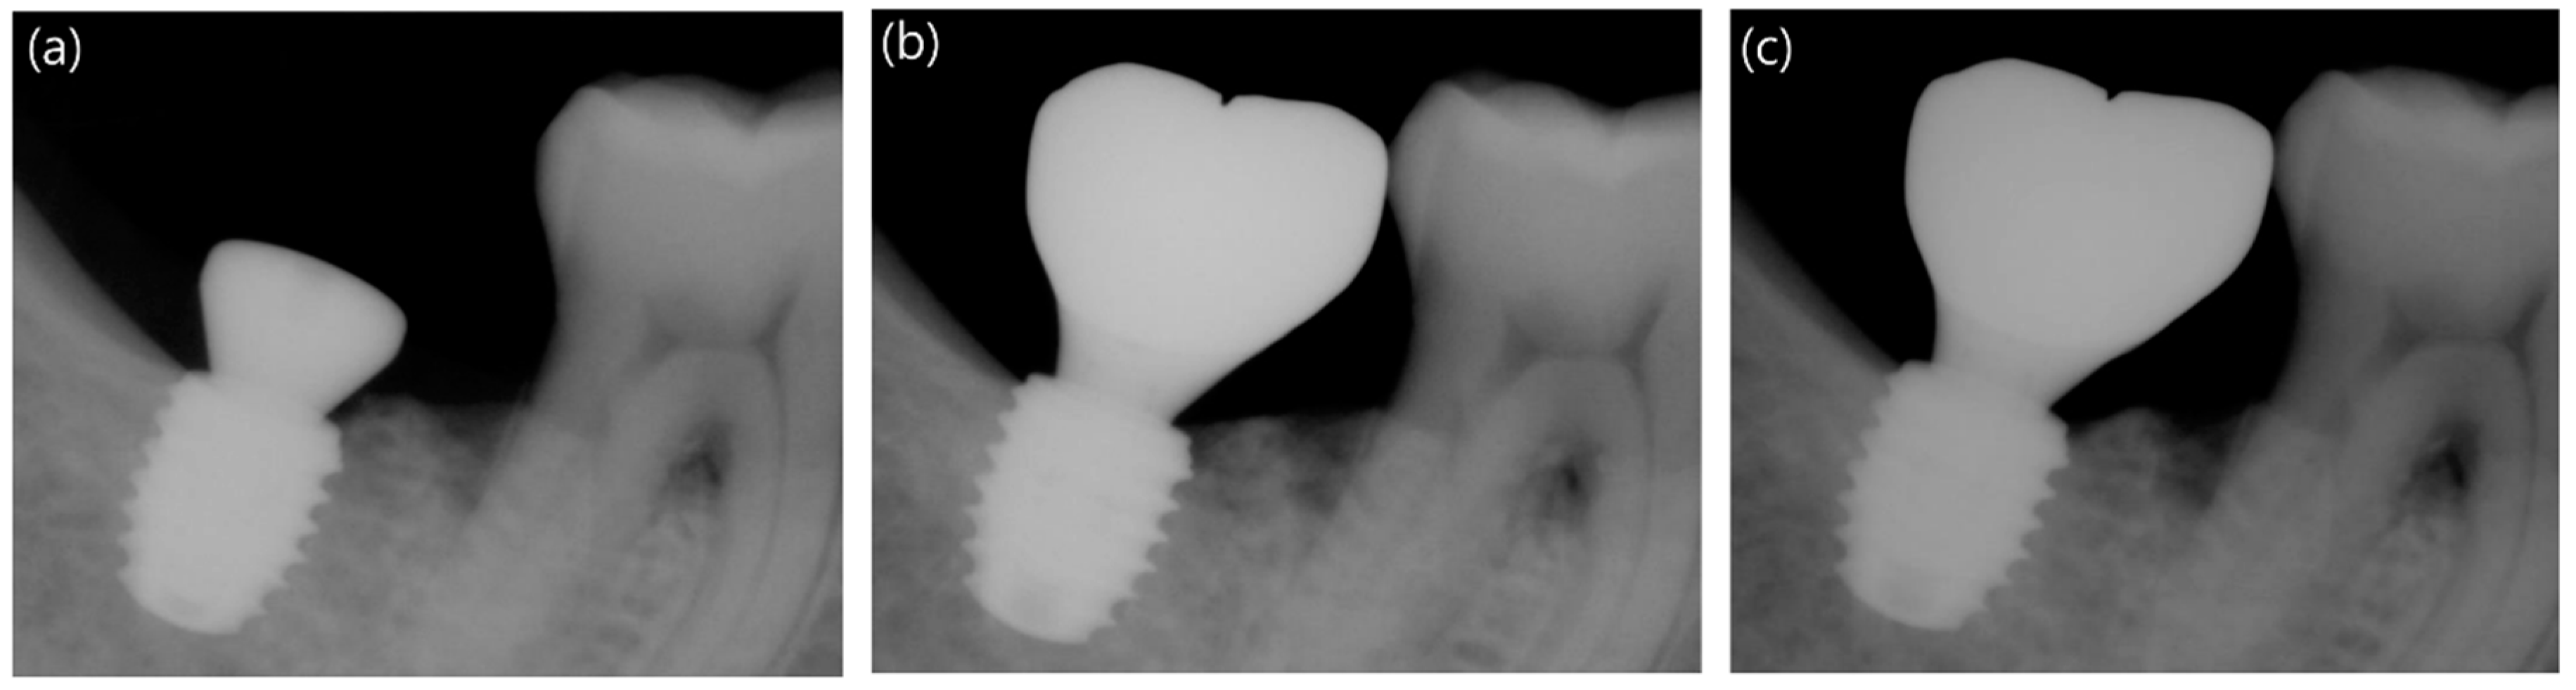

Peri-Implant marginal bone loss (PIMBL) was evaluated using standard periapical radiographs taken immediately after surgery and at 12 and 48 weeks after the implant installation (Figure 4 and Figure 5). In order to obtain the marginal bone level, the enlargement ratio of each image was calculated from the manufacturer-specified thread pitch of 0.9 mm that is known for each implant system used in this study. The distance from the fixture platform top (reference point) to the level of the alveolar bone crest was measured in the mesial and distal surfaces of the implant and converted to the actual value using the enlargement ratio. This value was then compared with the measurement taken at surgery (baseline).

Figure 4.

Standard periapical radiographs of implants placed in a patient in the control group (CMI IS-III active® long implant, Neobiotech Co., Seoul, Korea): (a) at surgery, (b) at 12 weeks, and (c) at 48 weeks.

Marginal bone loss after the implant insertion was evaluated for 46 implants using periapical radiographs taken at 12 weeks and 48 weeks after surgery (Table 3 and Figure 4 and Figure 5). The average marginal bone loss from the fixture platform top for the control and experimental groups was −0.07 ± 0.78 mm and 0.03 ± 0.63 mm after 12 weeks and 0.06 ± 0.82 mm and 0.05 ± 0.77 mm after 48 weeks, respectively. After a 12-week healing period, the distal surface exhibited slightly greater bone loss than the mesial side, but by the end of the trial, no differences in marginal bone loss between the two implant groups gained statistical significance (p-value > 0.05).